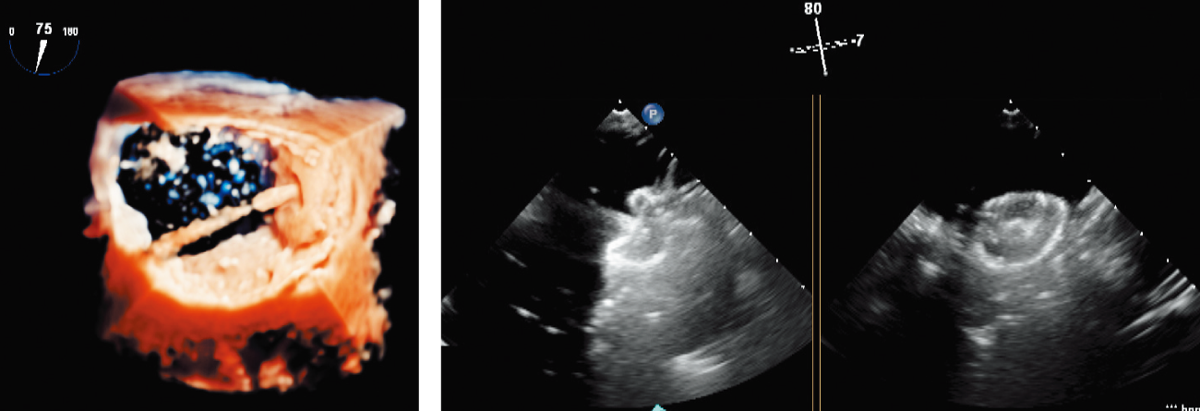

X線透視下、ならびに経食道エコーガイド下に、経⽪的⼼房中隔⽋損閉鎖術(ASD Closure: Atrial Septal Defect Closure)のシミュレーションを行うことが可能です。

欠損孔の大きさは標準で直径12mmにしてあります。サイジングバルーンで至適サイズのプラグを選択し、X線透視下にデリバリーカテーテルを左房内へ進め、経食道エコーガイド下に留置位置を確認しながら左⼼⽿内に閉塞⽤プラグを留置するという一連の⼿技を⾏うことができます。拍動ポンプで⾎流が再現されており、カテーテルを用いて造影を行うことも可能です。

拍動ポンプ

心拍数を30~120bpmの間で調整でき心臓モデル(冠動脈を含む)の拍動と循環を実現します。臨床の造影に近い画像を再現できます。